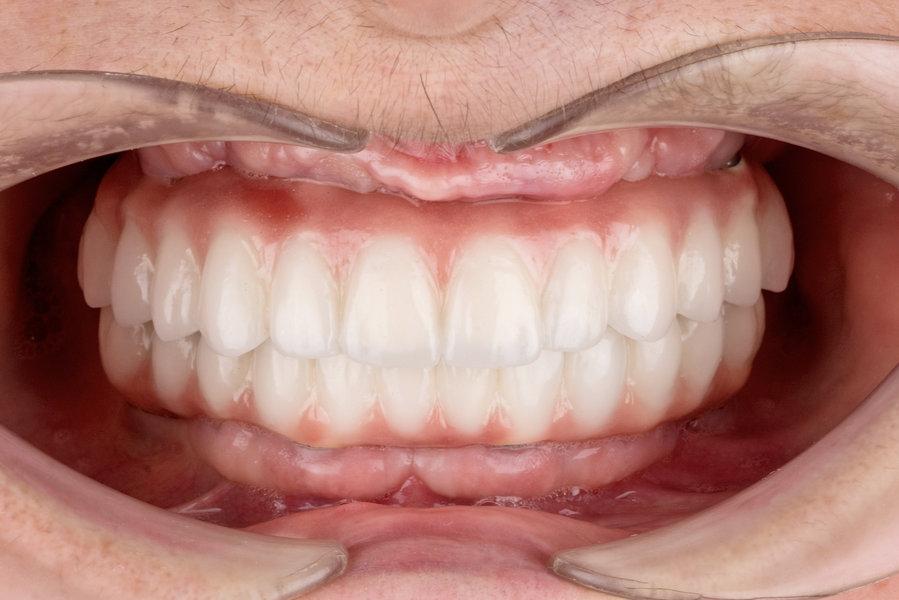

Cazuri clinice conceptul All-on-6

Caz 1